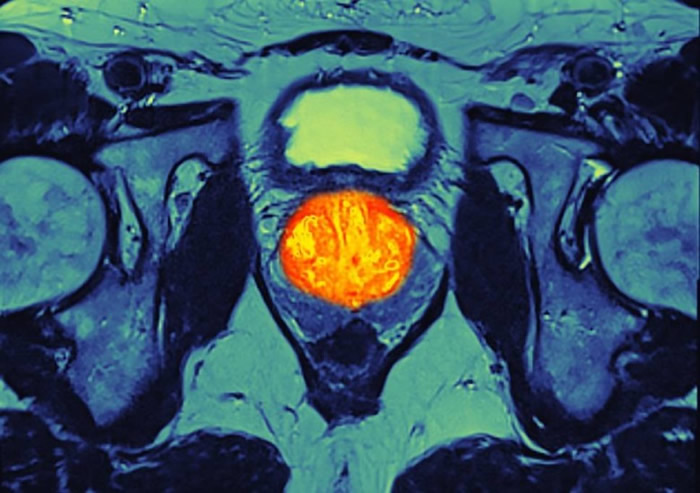

(蜘蛛网eeook.com报道)英国的医疗专家近日正着手研究一种新型免疫治疗药物,声称可以有助舒缓末期前列腺癌的病情,甚至可以阻止病情恶化。

这个由伦敦癌症研究学院及皇家马斯登医院联合进行的实验,以258名患上末期前列腺癌的男士为实验对象。团队发现,采用了这个新药后,有38%患者较预期多活一年,11%不再见到癌症有增长。研究人员目前正了解部分男士对这种新药较有效的原因。

这种针对免疫能力的治疗是通过药物来激活免疫系统,使其能够识别出癌细胞,过去这种方法已应用在其他末期的癌症治疗上。(东网驻英国记者章怡报道)